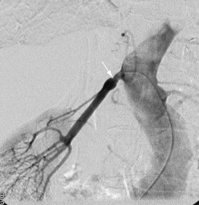

Renal arteriography

Conventional renal arteriography uses contrast medium to demonstrate the anatomy of the renal arteries. It is used to detect renal artery stenosis or aneurysms (Fig. 8.24). Therapeutic angioplasty may be performed at the same time. It can also be used in the diagnosis of tumours, but this is becoming less common with the increasing use of CT. A catheter is introduced into the femoral artery, through which contrast is injected into the renal artery and a series of radiographs are taken.

image

Fig. 8.24 Subtraction arteriogram of a right kidney. There is a single right renal artery with a significant stenosis at the ostium (arrow) with post-stenotic dilatation.